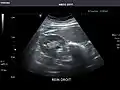

Abdominal Ultrasound (Full Exam)

STRUCTURED REPORT

(Technique: Transabdominal ultrasonography; Device: Toshiba Aplio XG)

Liver: Diffusely homogeneous and normal in echogenicity. No focal mass or contour nodularity. No intrahepatic biliary ductal dilatation.

Portal Vein: Patent main portal vein.

Gallbladder: No stones, wall thickening, or pericholecystic fluid.

Common Bile Duct: Nondilated measuring 1.3 mm at the level of the porta hepatis.

Pancreas: Visualized portions unremarkable.

Spleen: Normal in size.

Kidneys: Right and left kidneys measure 11.5 cm and 12 cm in length respectively. No hydronephrosis. Small left lower pole kidney cyst.

Ascites: None.

Aorta: Visualized portions normal in caliber, 16 x 15 mm.

IVC: Normal.

IMPRESSION:

Normal abdominal ultrasound.